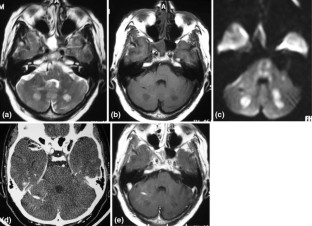

The advances in neuroimaging have improved clinicoanatomic correlations in patients with stroke. Junctional infarct is a distinct term, used to describe border zone infarcts of the posterior fossa. We presented computed tomography (CT) and magnetic resonance imaging (MRI) findings in a rare case of bilateral symmetrical junctional infarcts between the superior cerebellar artery (SCA) and posterior inferior cerebellar artery (PICA) territories. In addition to precise knowledge of arterial territories required to achieve accurate localization of ischemic lesions on CT and MRI, the radiologist must also be aware of radiologic features and geographic territories of cerebellar arteries and their junctional infarctions.

Fig. 1